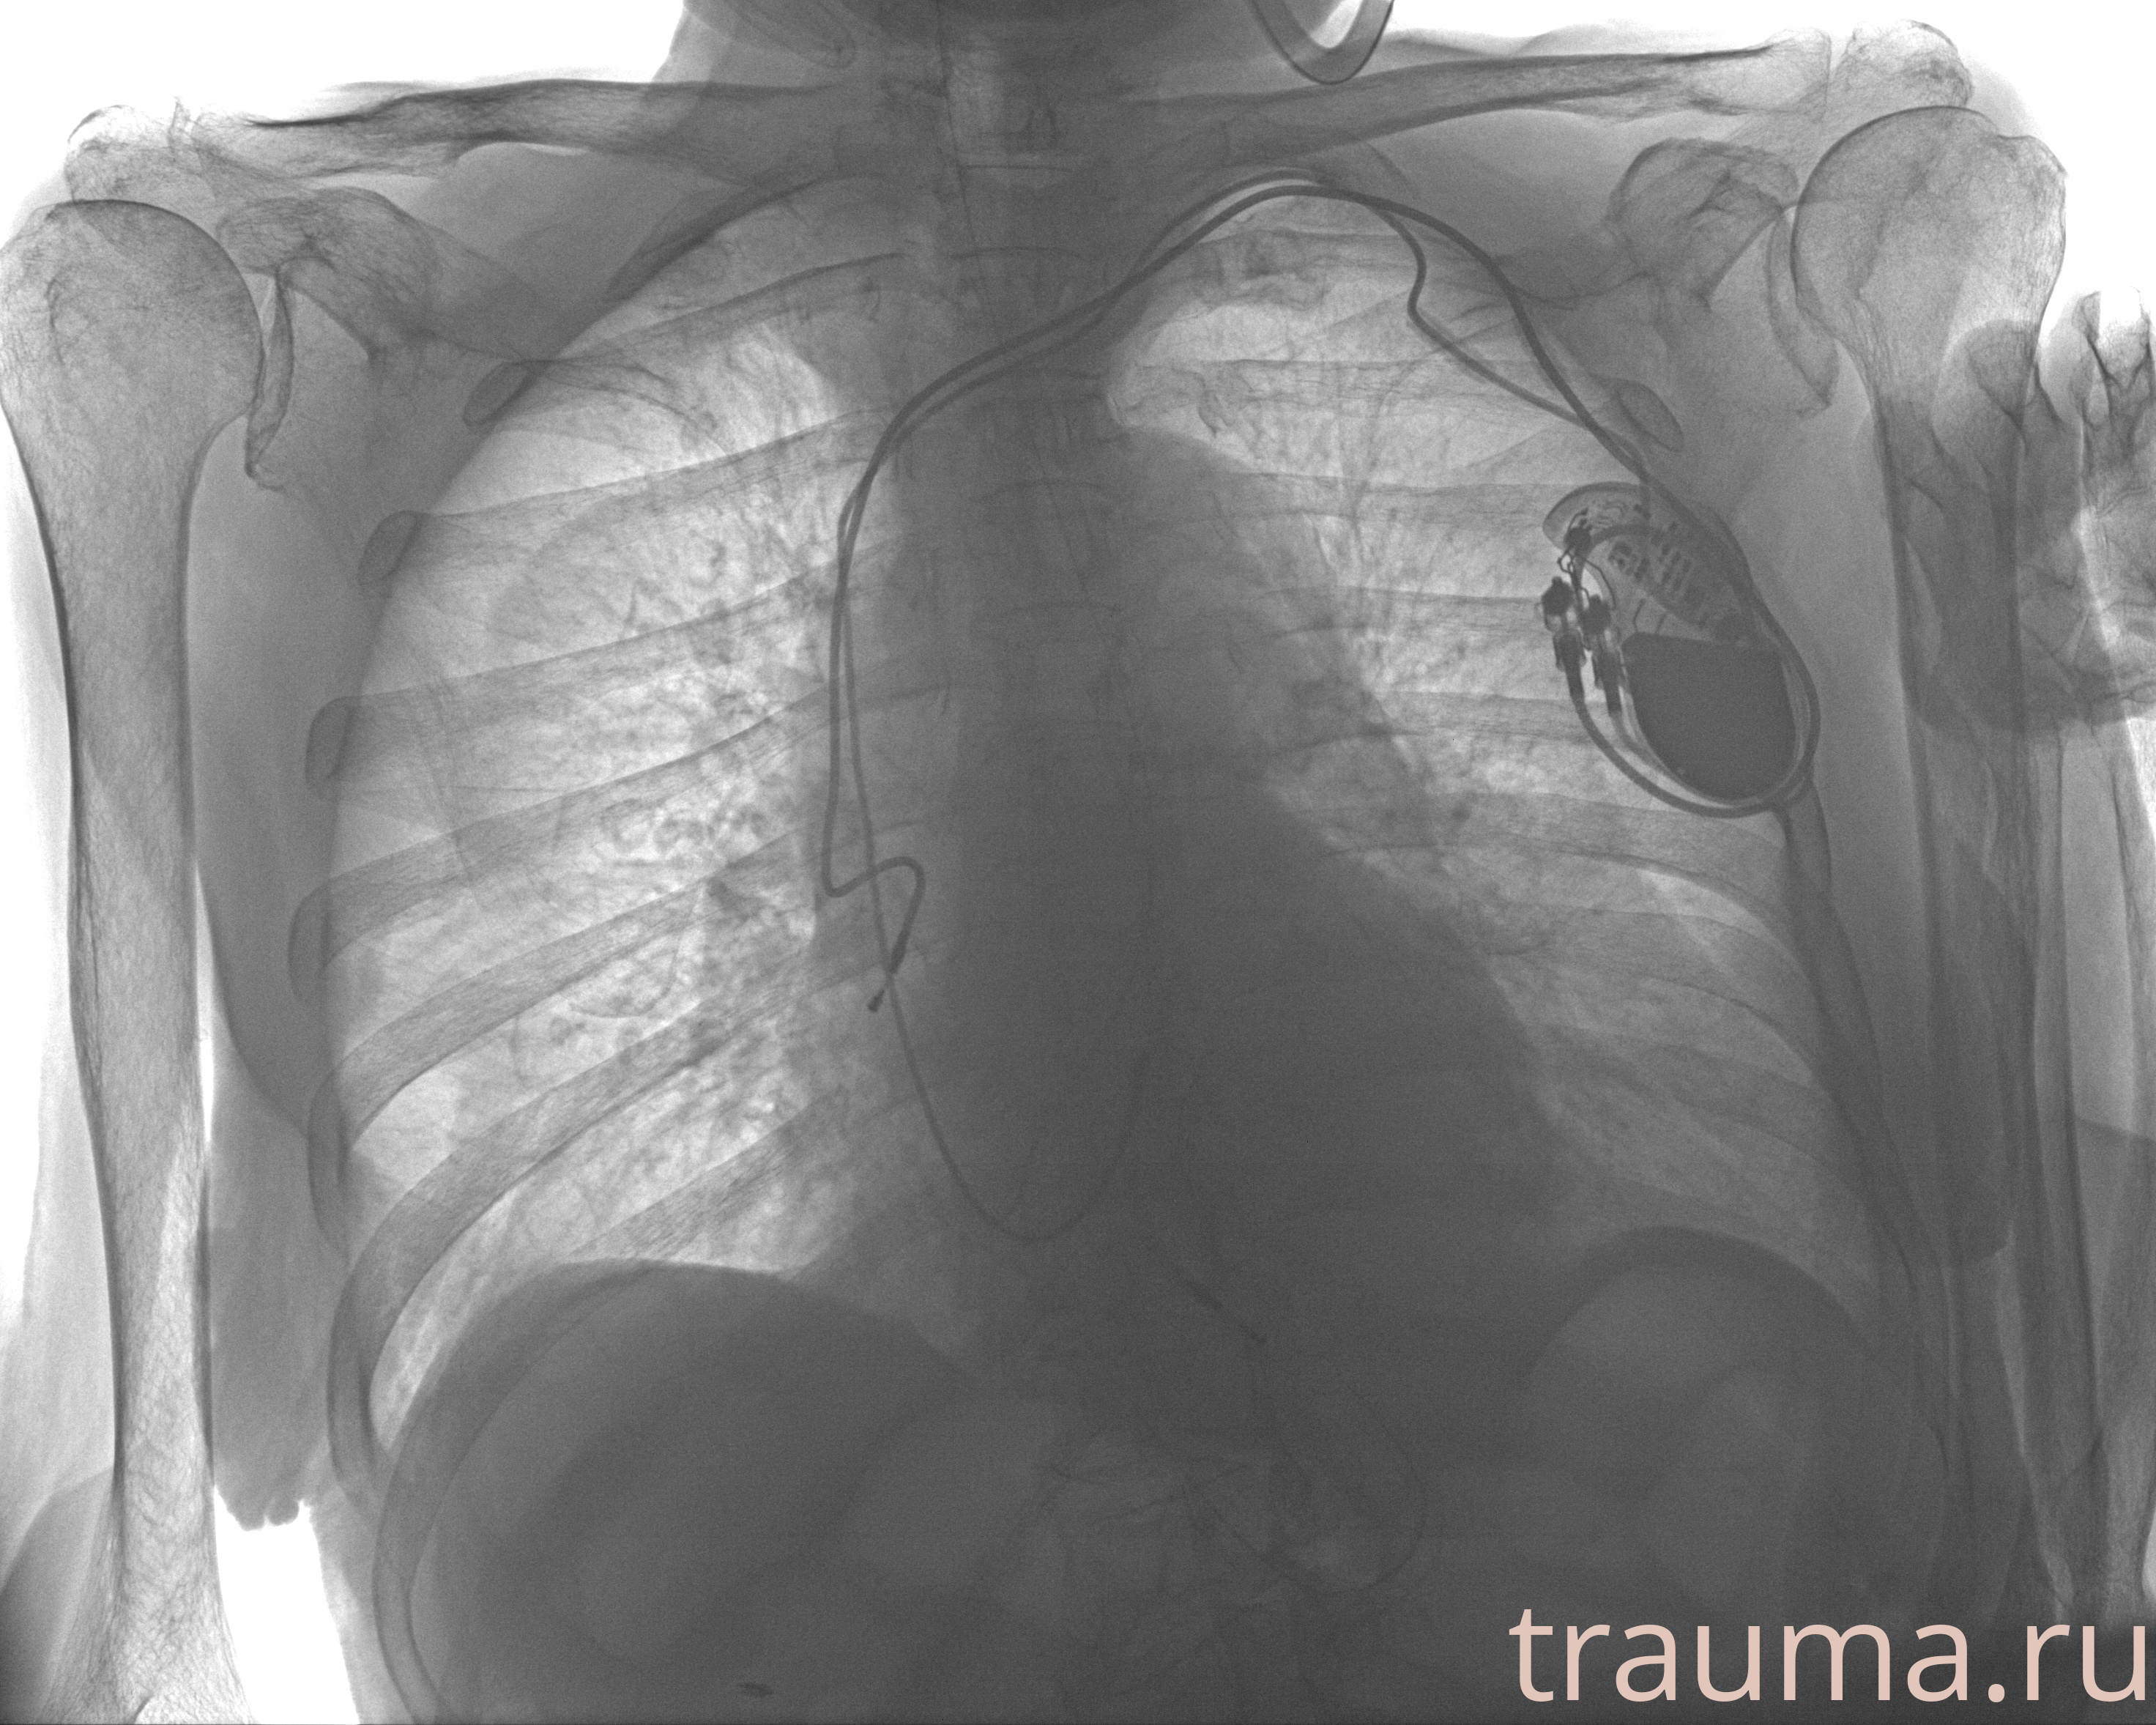

Рентген на дому: по вашему адресу приезжает врач-рентгенолог, травматолог-ортопед с мобильным рентгеновским аппаратом, проводит диагностику травмы или заболевания, делает необходимые рентгенограммы, дает рекомендации по дальнейшему лечению. Получить качественные снимки в домашних условиях возможно благодаря уникальной методике, разработанной МосРентген Центром для института  Склифосовского